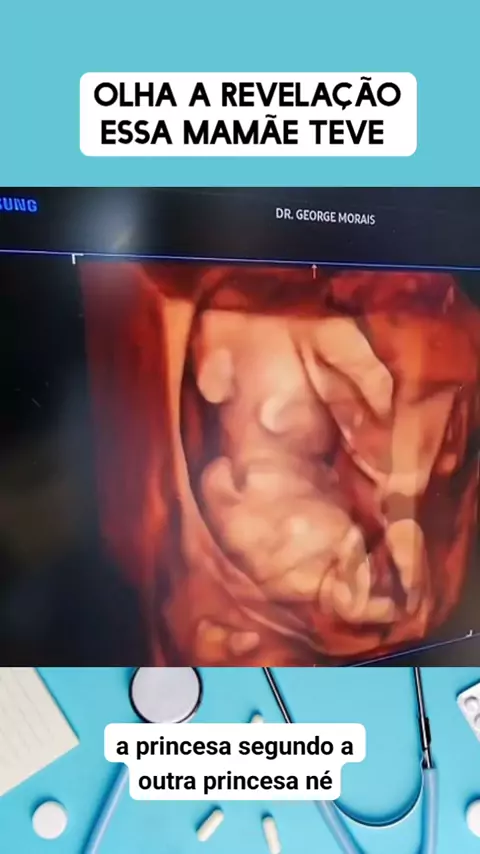

olha a reação dessa ultrassom #medico #medicina #Saúde #viraliza